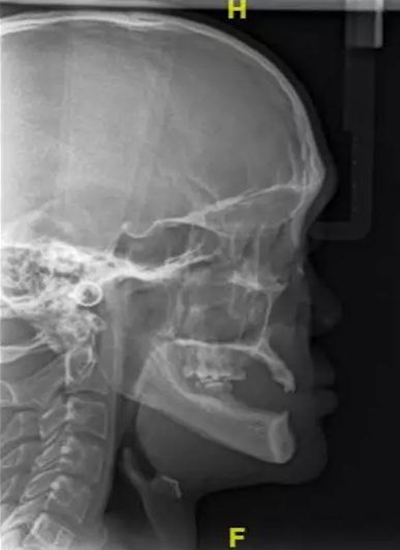

病例概要:患者,男,23歲,先天性多數(shù)恒牙缺失,外胚層發(fā)育不全,上下頜牙槽骨寬度及高度發(fā)育嚴(yán)重不足,佩戴傳統(tǒng)活動義齒固位穩(wěn)定效果差,幾乎沒有咀嚼功能,需通過種植修復(fù)來改善上述情況?;颊呒揖池毢?,所涉及的種植手術(shù)相關(guān)材料費(fèi)

用高,需要得到社會慈善機(jī)構(gòu)的幫助,才能獲得種植治療的可能。

病例資料:患者,男,23歲,先天性多數(shù)恒牙缺失,影響咀嚼和美觀功能。無恒牙拔牙史,無系統(tǒng)性疾病史,身體健康,無藥物過敏史。

??茩z查:口內(nèi)僅剩16,11,21,26,雙側(cè)上下頜乳牙E滯留,其余恒牙缺失,上下頜骨發(fā)育不足,缺牙區(qū)牙槽嵴呈刃狀,上下頜弓比例協(xié)調(diào)。CBCT顯示:上頜前牙區(qū)牙槽嵴寬度約2-3mm,骨高度約10mm;上頜后牙區(qū)可用牙槽骨高度僅1-2mm,左右側(cè)上頜

竇內(nèi)粘膜有明顯增厚。下頜牙槽骨寬度及高度嚴(yán)重不足,僅存有基骨。

病例難點(diǎn):

該病例為外胚層發(fā)育不全患者,先天性全口多數(shù)牙缺失,患者口內(nèi)僅剩4個恒牙,4個乳牙,勉強(qiáng)維持咬合功能。牙槽骨發(fā)育嚴(yán)重不足,垂直向和水平向骨缺損顯著。如果應(yīng)用常規(guī)的種植方法需要在前牙區(qū)和后牙區(qū)進(jìn)行大范圍的植骨手術(shù),整個治療周

期將長達(dá)一年或以上,費(fèi)用高。這類患者口內(nèi)來源的骨量非常有限,如果進(jìn)行自體骨移植,則需要另外增加一個口外供骨區(qū),增加了患者的痛苦,治療效果也難以保證。此外,經(jīng)驗(yàn)表明,外胚層發(fā)育不全的患者行骨增量往往成骨效果差,療效甚微。

由于牙槽骨寬度嚴(yán)重不足,短種植體不適用于此類患者。因此,上述病例屬于難度極高的種植對象,讓很多種植醫(yī)生一籌莫展。